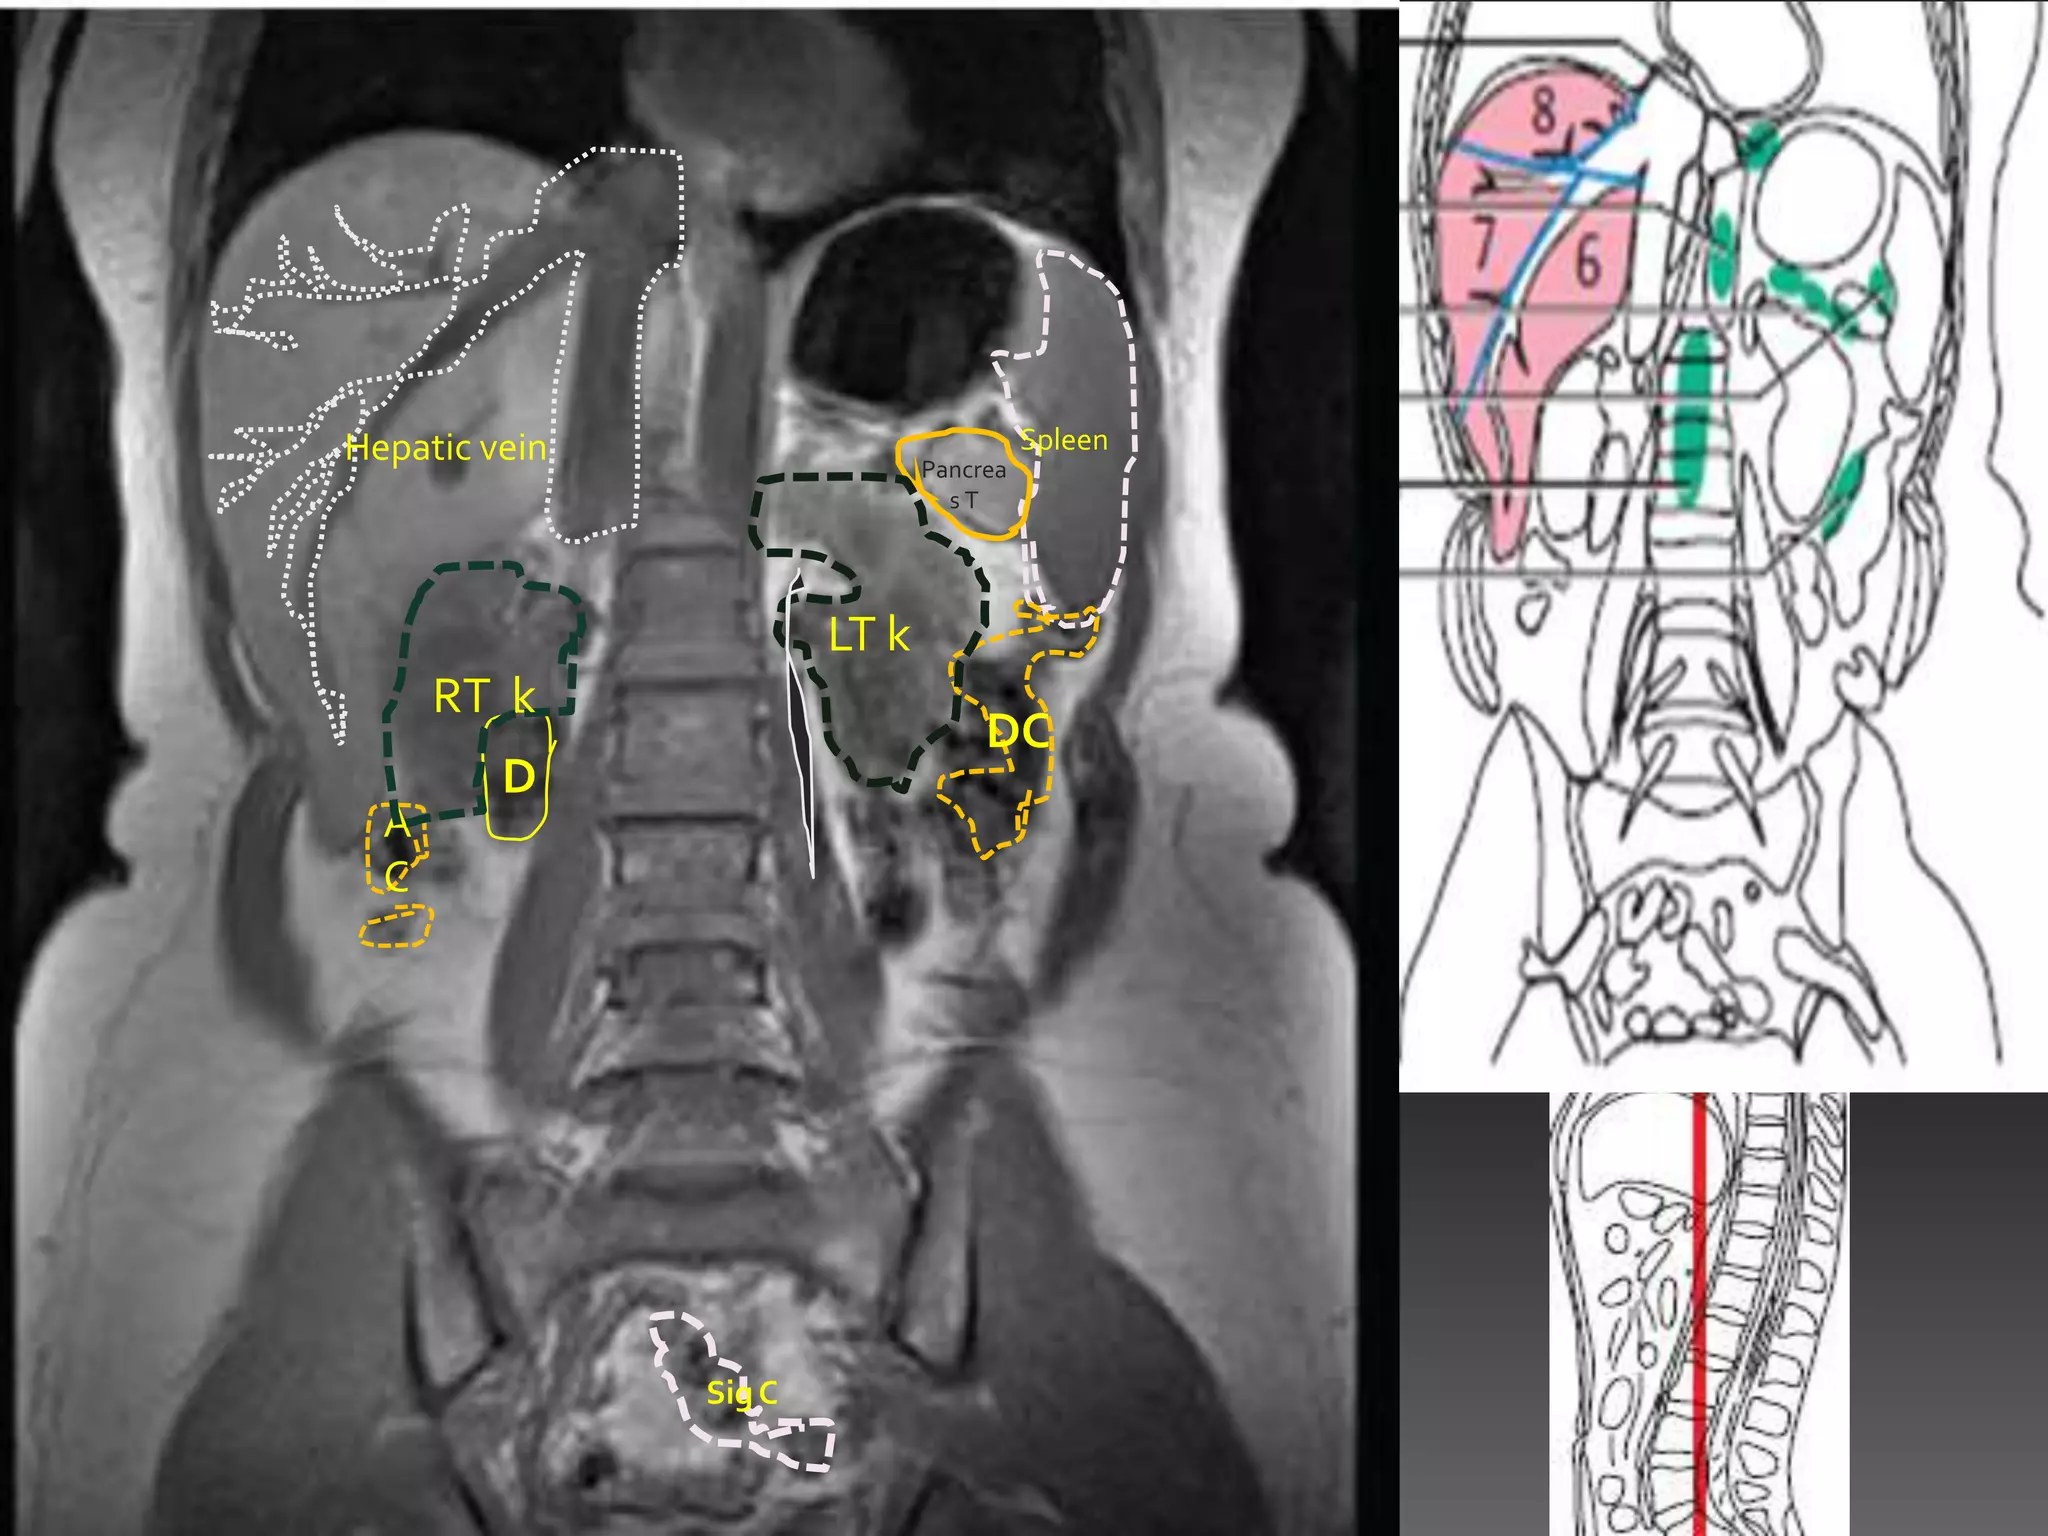

Hepatic vein                            Spleen

Pancrea

sT

LT k

RT k

DC

D

A

C

Sig C